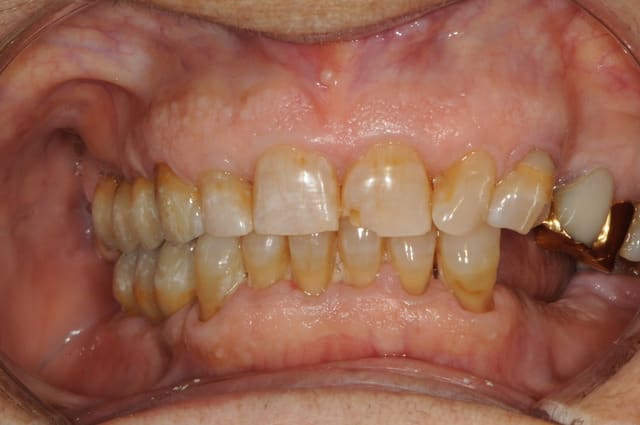

charlie est un blanchiment interne + compo palatin

rien en vestibulaire à part blanchiment complémentaire (à la base la dent nécrosée était vraiment très foncée)

la photo est à l'envers

Mais sinon vous avez tous raison : c'est bien la 21 (donc 41 pour D57) sauf toi Jeamba qui as eu une hésitation : tu étais plus proche avec ta 12 en verlan

technique : perborate 2 séances (3 jours à chaque fois) puis compo teinte bleaching dans la cavité et une séance de zoom en complémentaire externe